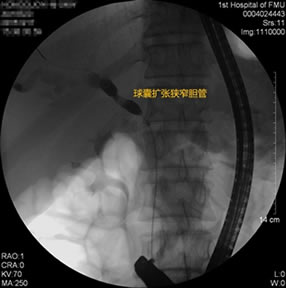

胃毕-Ⅱ术后球囊扩张狭窄胆管 胃毕-Ⅱ术后支架植入 胃毕-Ⅱ术后胆管胰管扩张